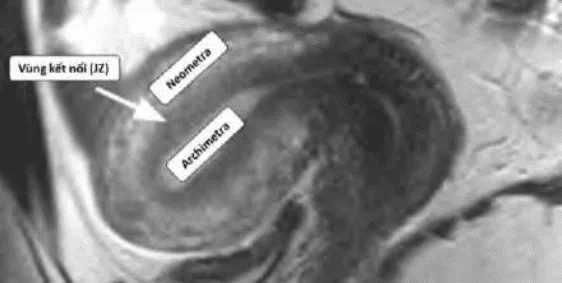

Thuyết tử cung hai nguồn gốc: Tử cung phát triển từ hai nguồn Muller và trung mô, gặp nhau tại vùng kết nối (JZ). Adenomyosis xuất phát từ chồng lấn bất thường tại JZ.

Hình ảnh “Tử cung bình thường trên MRI”.

Hình ảnh “Adenomyosis trên MRI”.